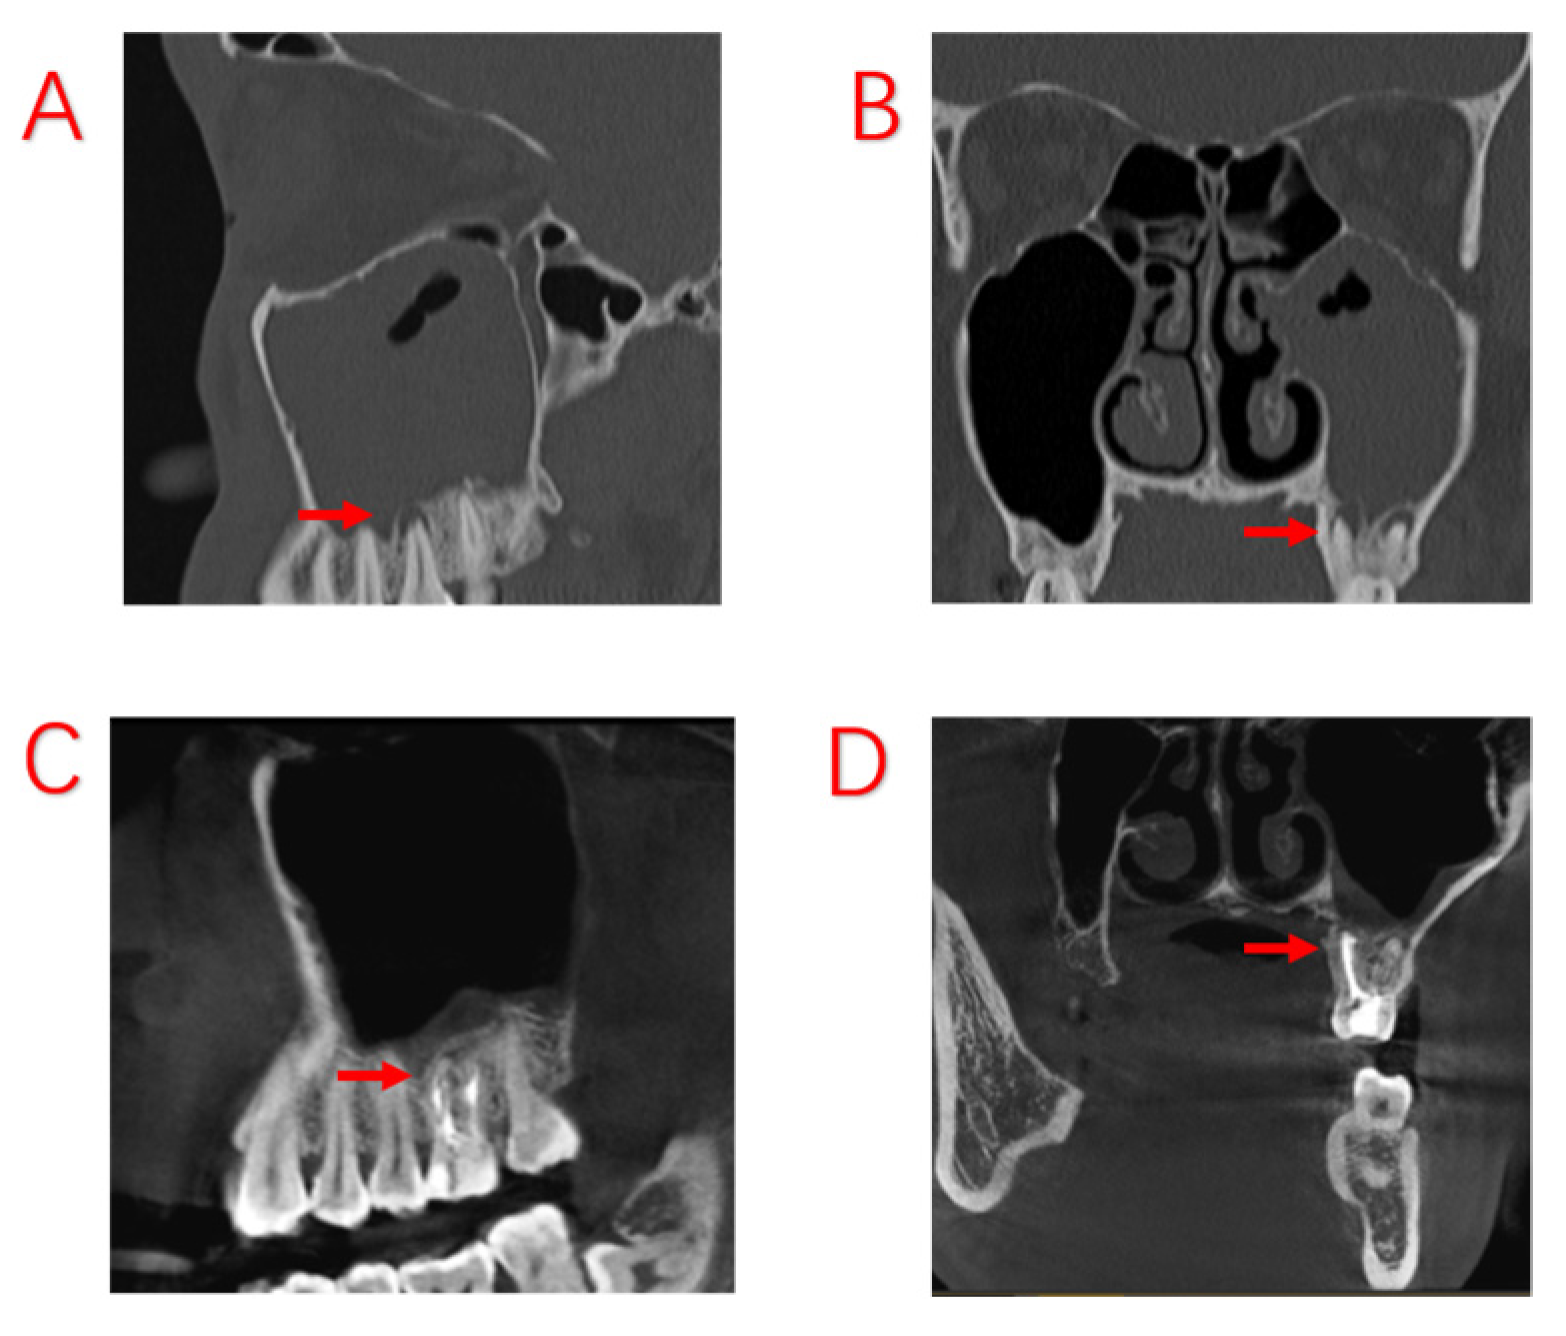

Figure 2.

Odontogenic sinusitis due to periapical inflammation. Symptoms disappeared after root canal treatment; no ESS was performed. (A,B): Before root canal treatment, the patient developed a purulent discharge with a foul odor and obstruction of the maxillary sinus opening. (C,D): After root canal treatment, infection of the dental pulp was controlled and the symptoms of sinusitis had disappeared, with the mucosa of the maxillary sinus returning to normal. Red arrows indicate sites of apical inflammation.